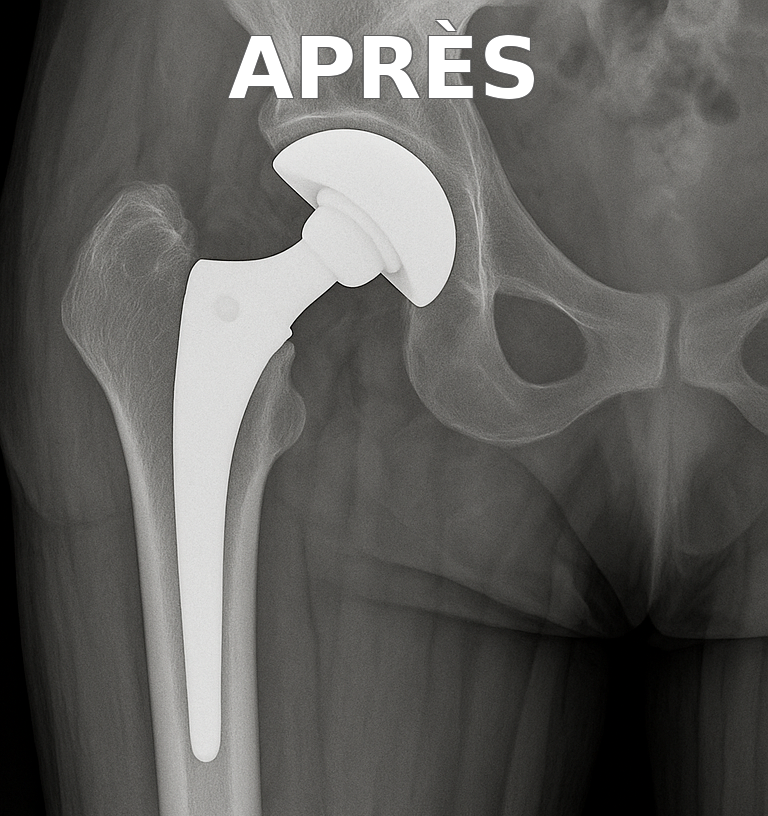

Illustration radiologique

Prothèse de hanche